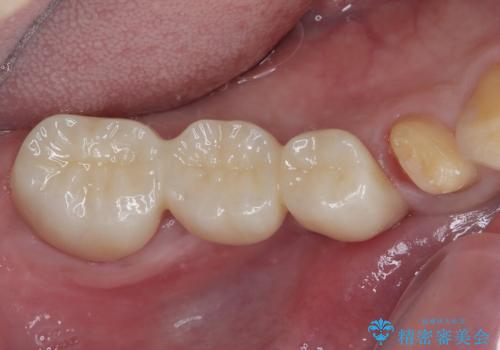

詰め物が割れた フルジルコニアクラウン

- 左下の4番目のセラミックの詰め物(セラミックインレー)が欠けたとのことで来院された患者様です。以前にセラミックの詰め物の治療を行い、噛み合わせが強く割れてしまっていました。今回はセラミックの詰め物のやり替えだとまた欠けてしまう可能性があるのでフルジルコニアクラウンでの治療を行うことにしました。拡大鏡視野下でセラミックの詰め物、虫歯を除去しフルジルコニアクラウンに適した形に整えました。

歯と歯茎の間に圧排糸と呼ばれる糸を入れてシリコーン印象を行いました。

見た目、機能面ともに満足していただけました。

噛み合わせが強い方なので今後はセラミックが割れないようにナイトガードを使っていただきながら、定期的にクリーニングで通ってもらう予定です。